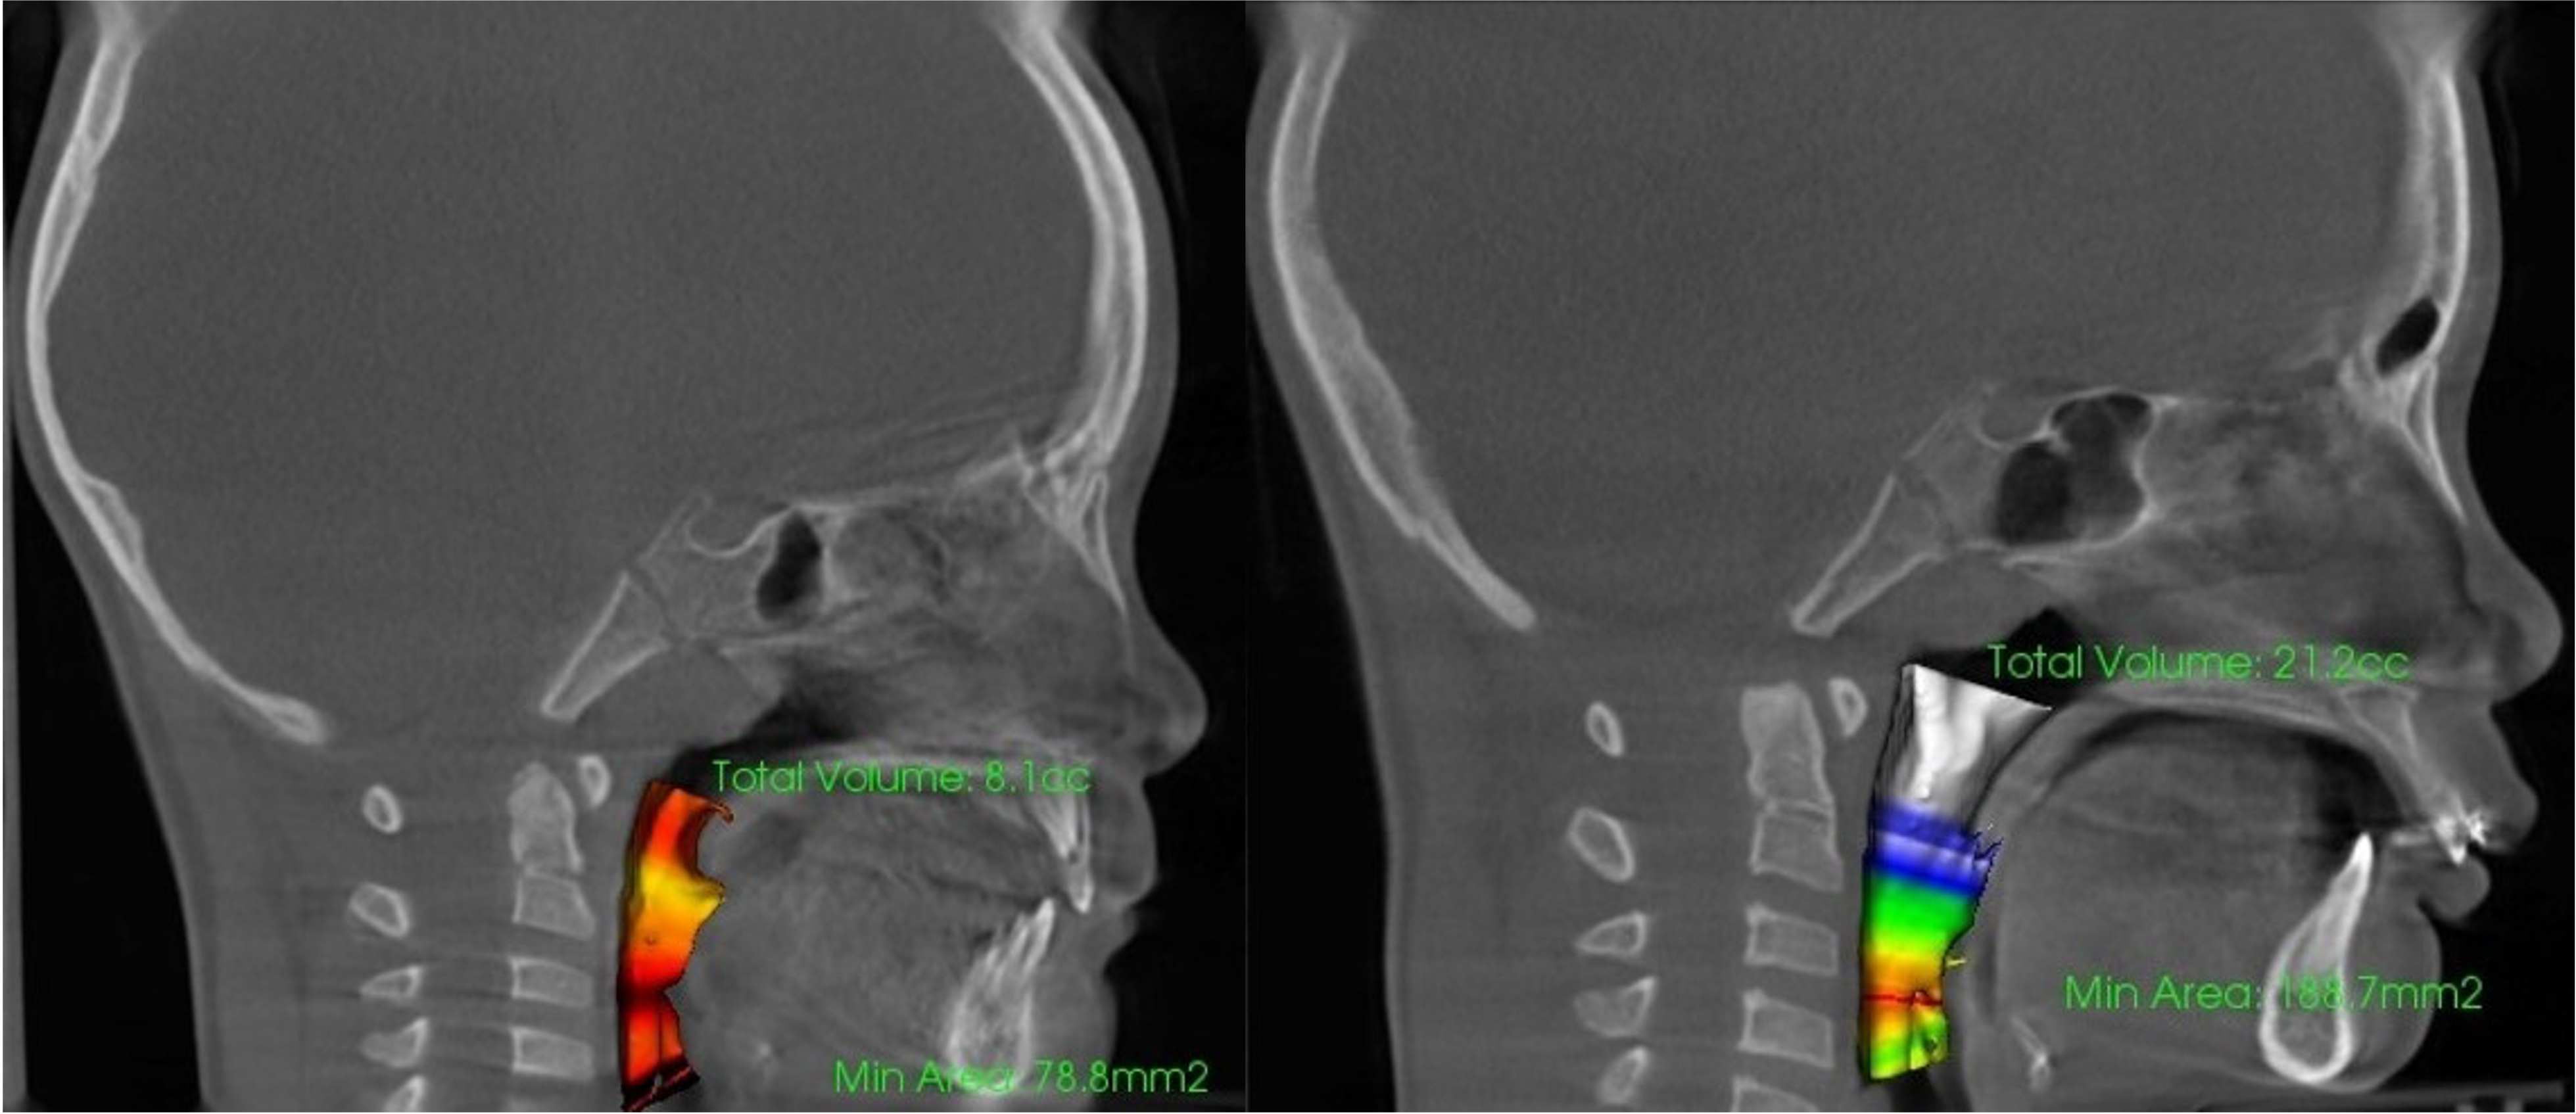

RAMPAによる気道容積の変化イメージ

これらを改善するためには、根本となる骨格への介入が必要不可欠です。

ランパセラピーの特徴は、上顎骨を上前方方向へと3次元的に牽引し、下方に向かっていた中顔面の成長を健全方向へと変化させ、成長を促せることにあります。ここが非常に特殊なアプローチです

この「歪みのない健全な顎骨」への成長誘導によって、気道や鼻腔が拡がり、呼吸器系疾患や耳鼻系疾患に対しての改善が期待できます。